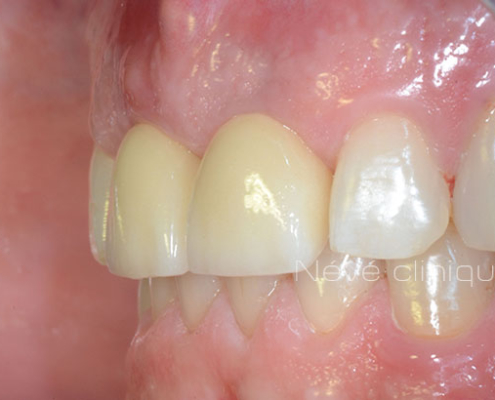

Le jour de votre chirurgie, nous mettons en place le guide sur vos dents restantes ou le vissons sur votre mâchoire. Nous réalisons le forage à travers le guide et plaçons les implants dentaires. Ensuite, nous retirons le guide et vissons immédiatement la prothèse provisoire préparée à l’avance.